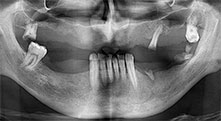

Pr Bratu : Nous avons volontiers recours à la technique sandwich pour les augmentations mandibulaires latérales. La préparation d'un couvercle osseux est réalisée à l'aide de la scie piézoélectrique et le fragment crestal est fixé à l'aide de microvis. Nous plaçons un mélange de matériau de substitution osseuse autologue et xénogénique entre les deux. Cela fonctionne très bien. Il faut toujours s'assurer que les coupes verticales aient des dimensions suffisantes lors du clivage de la crête alvéolaire dans la mandibule. Sinon, l'os risque de se casser facilement.